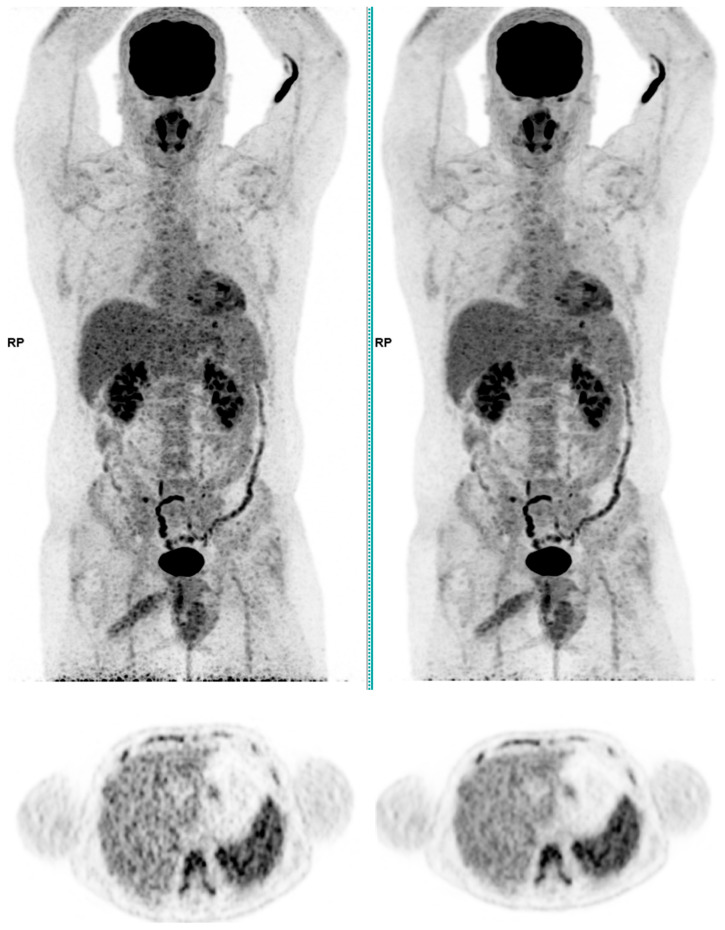

This study assesses the clinical deployment of SubtlePET™, a commercial AI-based denoising algorithm, across three radiotracers-18F-FDG, 68Ga-PSMA-11, and 18F-FDOPA-with the goal of improving image quality while reducing injected activity, technologist radiation exposure, and scan time. A retrospective analysis on a digital PET/CT system showed that SubtlePET™ enabled dose reductions exceeding 33% and time savings of over 25%. AI-enhanced images were rated interpretable in 100% of cases versus 65% for standard low-dose reconstructions. Notably, 85% of AI-enhanced scans received the maximum Likert quality score (5/5), indicating excellent diagnostic confidence and noise suppression, compared to only 50% with conventional reconstruction. The quantitative image quality improved significantly across all tracers, with SNR and CNR gains of 50-70%. Radiotracer dose reductions were particularly substantial in low-BMI patients (up to 41% for FDG), and the technologist exposure decreased for high-exposure roles. The daily patient throughput increased by an average of 4.84 cases. These findings support the robust integration of SubtlePET™ into routine clinical PET practice, offering improved efficiency, safety, and image quality without compromising lesion detectability.